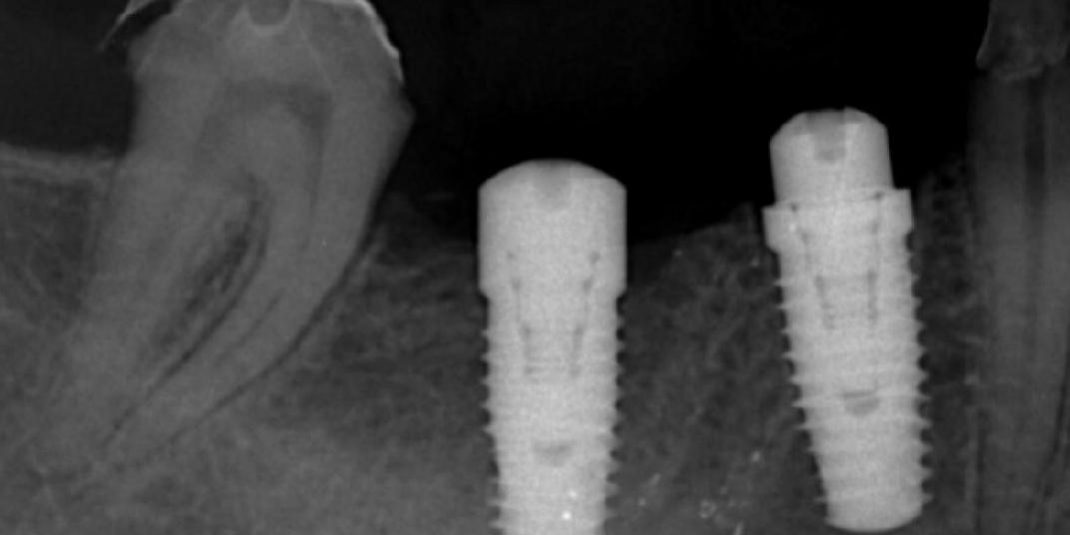

Biomet 3i tapered dental implants ในซี่ 46 เรียกว่า platform match คือมีขนาดพอดีกับขนาดของ fixture

ส่วนในซี่ 45 นั้น คือ platform switching (รากเทียมทั้งคู่มีขนาด 5 มม เท่ากัน แต่ในตำแหน่งใช้ healing ขนาด 4.1 มม)